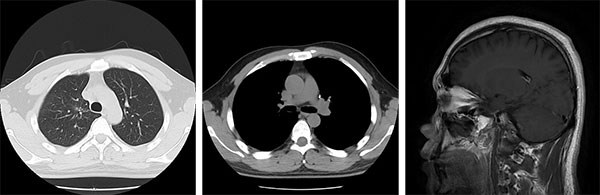

2016年5月,31岁的小申连续多日出现咳嗽、痰中带血症状,左侧后背还时常隐痛。起初他以为是熬夜工作劳累所致,直到症状持续加重,才在家人催促下前往当地医院就诊。胸部CT显示左肺上叶存在占位性病变,进一步检查后发现,癌灶已转移至右肺及纵隔淋巴结,头部MRI更提示脑部存在多发转移灶;支气管镜活检最终确诊为肺腺癌。“拿到病理报告,被医生告知所患疾病是晚期肺癌(Ⅳ期)伴脑转移的那天,我在医院走廊里坐了很久,反复问自己:为什么是我?”无烟酒习惯、无家族肿瘤病史的小申在医院走廊枯坐良久,始终无法接受自己已是晚期癌症的事实。

“刚开始服药时,心里总有些忐忑,怕效果不如预期。”服药第3天,咳嗽症状明显减轻;8周后复查,胸部CT显示肺部病灶显著缩小,阻塞支气管的肿瘤组织基本消失;70天,头颅核磁也提示脑转移灶体积缩小、部分微小病灶完全消失。小申的抗癌小本本上记录着他每一天的状况改善。就这样,在治疗的第三个月,小申就重新回到了工作岗位,气色越来越好,变得和常人无异。

治疗前(2016年12月)

治疗后(2025年06月)